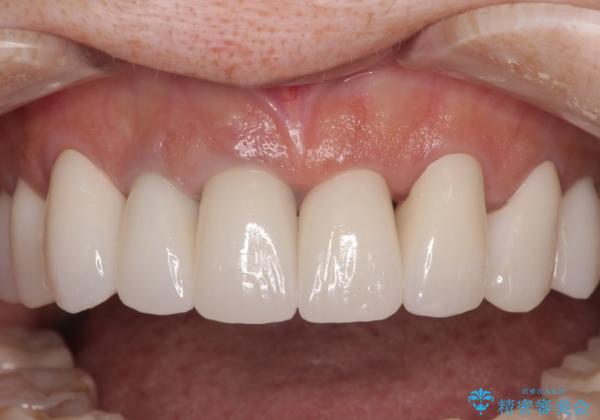

不釣り合いで境目の露出した前歯 オールセラミッククラウンによる審美歯科治療

- 前歯のセラミックが欠けたり色調が不揃いであったりすることを気にして来院された患者様です。

20年以上前から、むし歯になったり詰め物が欠けたりする度に部分的に処置を行ってきたそうですが、この際統一感のある前歯にしたいとのことで、上顎前歯9本をオールセラミッククラウンによる補綴治療を行うこととしました。

色調が統一されるだけでなく、歯肉ラインに見えていた茶色の境目も綺麗に改善されました。